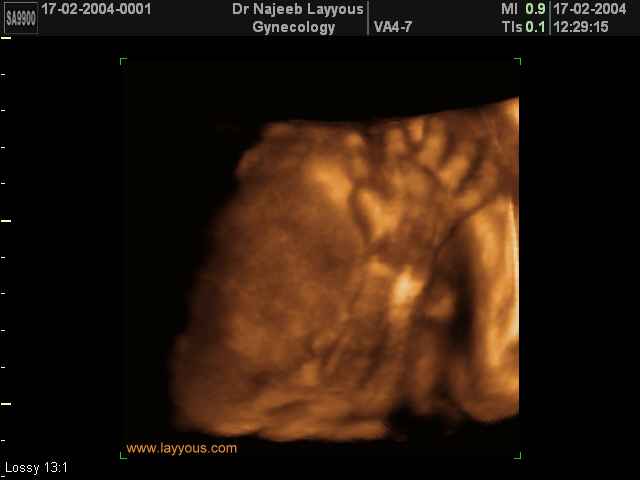

3D Ultrasound Scan Photos of Fetal Limbs | Dr N Layyous

3D Fetal Limbs Ultrasound Scan Photos